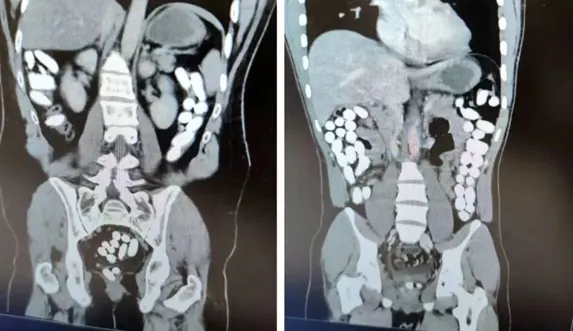

Erzincan İl Emniyet Müdürlüğü Narkotik Suçlarla Mücadele Şube Müdürlüğü ile Kaçakçılık ve Organize Suçlarla Mücadele Şube Müdürlüğü ekiplerince yapılan çalışmada; Uygulama noktasında durdurulan yolcu otobüsünde yolcu olarak bulunan İran uyruklu A.G. (25) ve E.P. (21) İsimli şahıslara alınan karara istinaden yapılan tomografi çekiminde mide ve bağırsak kısmında uyuşturucu olabileceğini değerlendirilen çokça yabancı cismin olduğu görüldü. Yapılan tetkikler neticesinde A.G. (25) isimli şahıstan 100 parça halinde 847,64 gr gelen Afyon Sakızı, E.P. (21) isimli şahıstan 142 parça halinde 1071,80 gr gelen Afyon Sakızı ele geçirildi. Şüpheliler emniyetteki işlemlerinin ardından sevk edildiği adliyede “Uyuşturucu Madde Ticareti Yapmak” suçundan tutuklanarak cezaevine gönderildi.